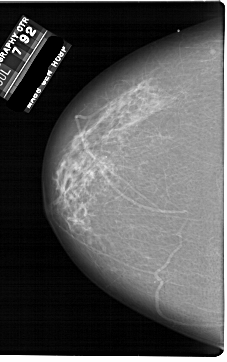

A_1861_1.RIGHT_MLO

RIGHT_CC LINES 6871 PIXELS_PER_LINE 4051 BITS_PER_PIXEL 12 RESOLUTION 43.5 OVERLAY